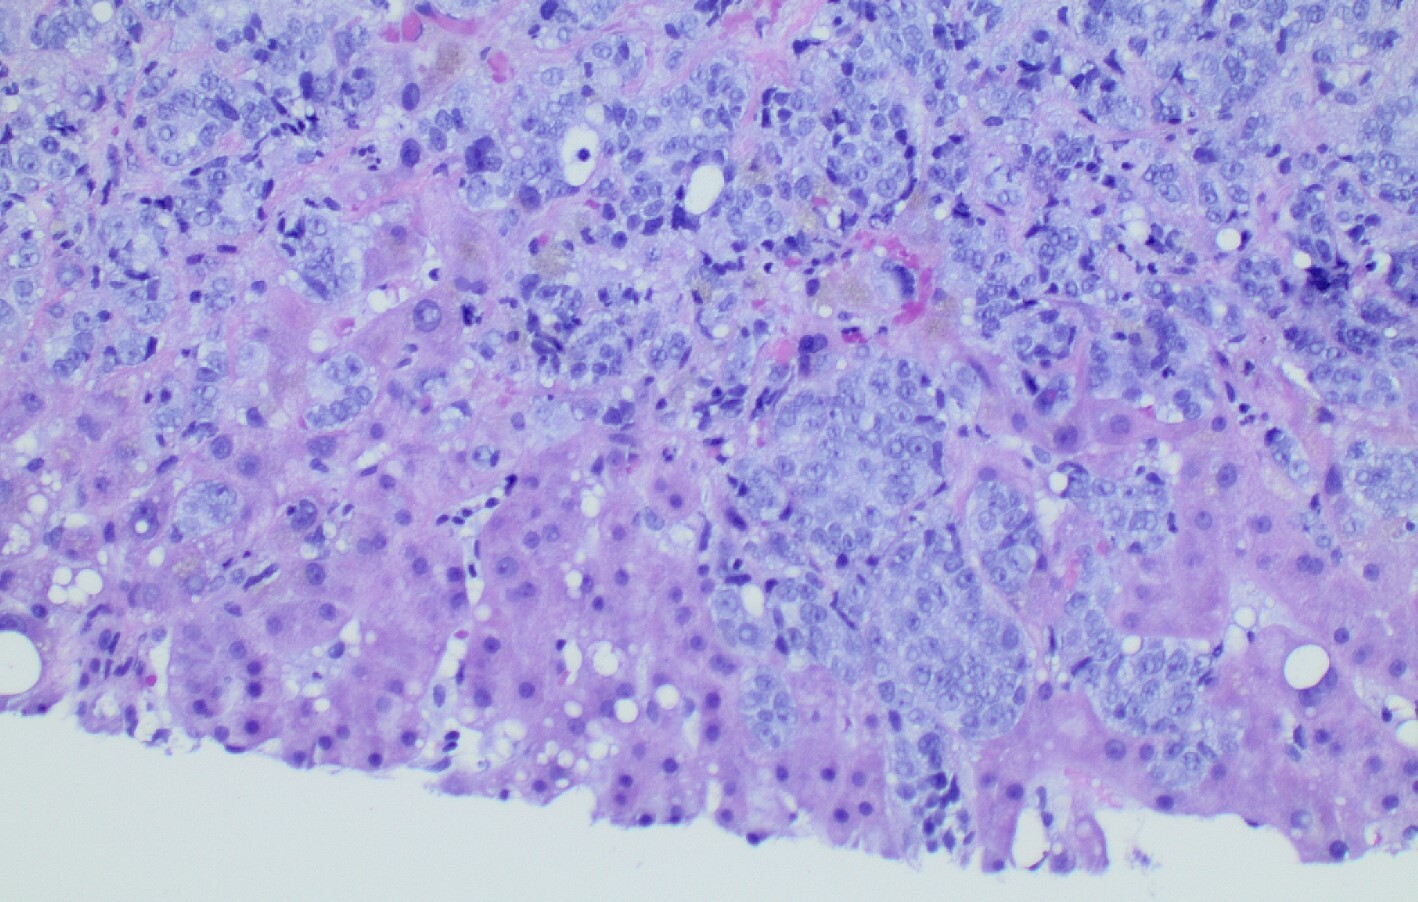

Diagnostic paracentesis was performed and revealed an ascitic protein of 0.9 g/dL, and serum-ascites albumin gradient was calculated to be 2.8. Given his prior history of docetaxel use, the decision was made to proceed with a trans-jugular non-targeted liver biopsy to rule out medication induced hepatic veno-occlusive disease. Hepatic venous pressure gradient was found to be elevated at 32 mmHg. The liver biopsy revealed infiltrative adenocarcinoma from known primary prostate cancer with immunohistochemical staining significant for positive NKX 3-1 and negative CK7 and CK20 (Figures 1-5). The patient was diagnosed with ALF secondary to infiltrative prostate cancer and did not meet transplant criteria due to malignancy. Considering the information provided via the liver biopsy, it was determined the lutetium (177Lu) vipivotide tetraxetan therapy would be ineffective. After extensive conversation, the patient and his family opted for home hospice to spend valuable time with loved ones. The patient was discharged after a total hospital stay of 6 days. He expired less than 2 weeks after discharge.